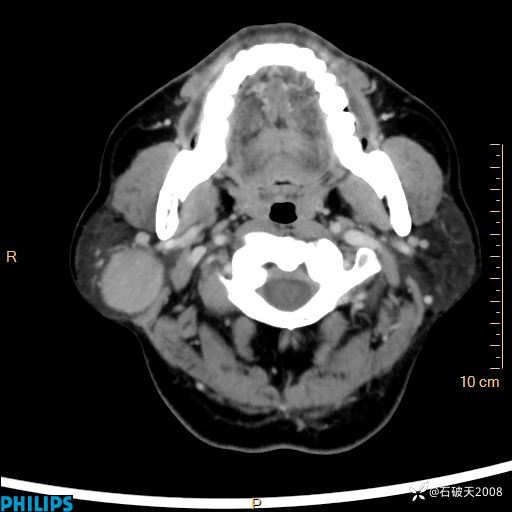

动脉期